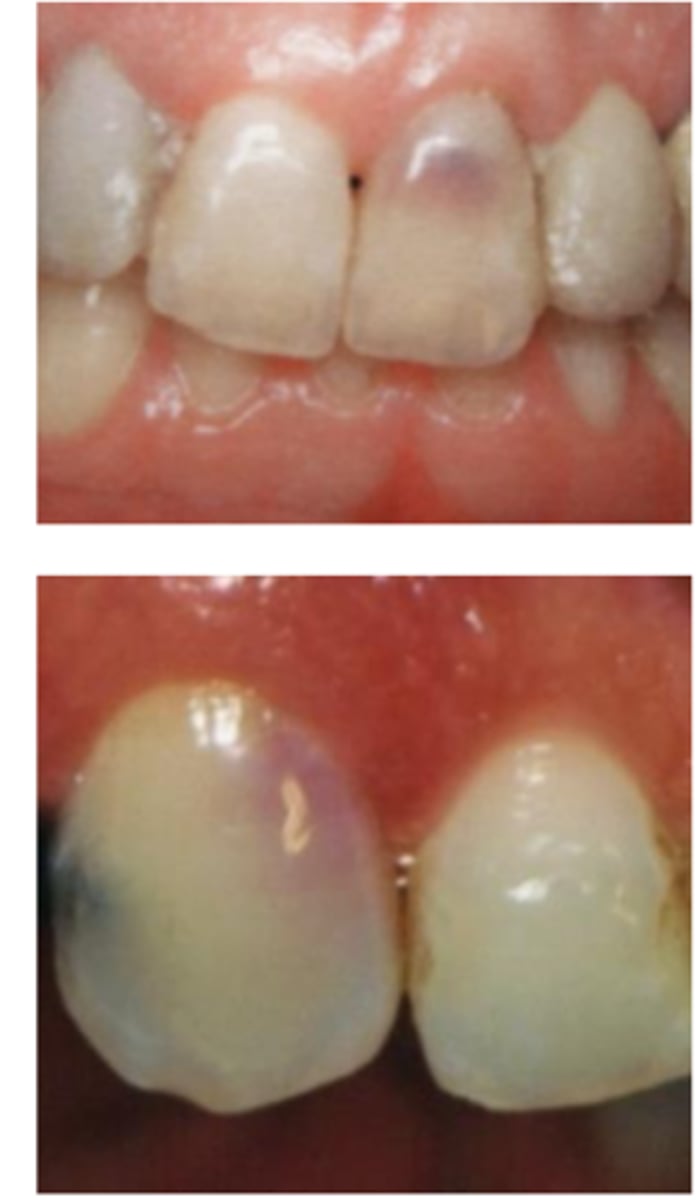

External cervical resorption (Invasive Cervical Resorption)

ID the type of resorption:

- Often asymptomatic until late stages, and may be misdiagnosed as caries

- Possible pink spot in the cervical aspect of the tooth, near gingival margin

- Often hemorrhagic on probing

- Feels hard and scratchy when probed (unlike subgingival caries which feels sticky)

A patient presents asymptomatic with a pink spot in the cervical aspect of the tooth, near the gingival margin. Upon probing, the pocket is hemorrhagic and feels hard/scratchy. What is the most likely diagnosis?

- Usually an incidental radiographic finding, especially for less advanced lesions

- Variable appearances; may be a well-defined or irregular radiolucency around the cervical aspect of the tooth

- A portal of entry is always present in the cervical region of the tooth

- The chamber/canal outline is often visible as the innermost layer of predentin around the chamber is not resorbed